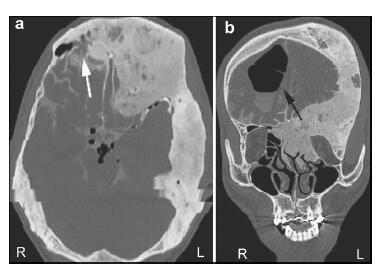

20161117201031  Figure 3 A CT scan demonstrating a contoured bone and enlarged cranial cavity. (a, b) Before the fistula repair surgery. (c, d) After the fistula repair surgery.